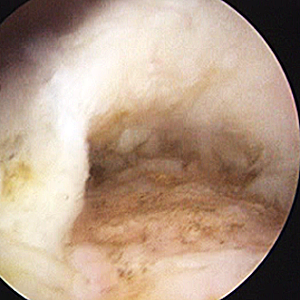

整形外科における手術の役割 肩腱板断裂治療のアルゴリズム 不全断裂 小断裂 中~大断裂 一次修復不能広汎性断裂 保存療法(リハビリ:運動療法/物理療法) 手術療法 関節鏡下腱板修復術 腱移行術、腱移植術、リバース型人工関節 腱板断裂の治療の基本は保存療法ですが、それが反応しない場合には、関節鏡下腱板修復術が適応されます。 修復前 修復後 関節鏡下腱板修復術は「肩に小さな穴を数か所開け、関節鏡で中をのぞきながら縫い合わせる方法」で、私の得意分野です。 不全断裂 小断裂 中~大断裂 一次修復不能広汎性断裂 保存療法(リハビリ:運動療法/物理療法) 手術療法 関節鏡下腱板修復術 腱移行術、腱移植術、リバース型人工関節 縫いきれないほどの大きな断裂には、腱の移植や人工関節が必要になります。 手術を望まない方へは、間葉系幹細胞を用いた再生医療の提供に取り組んでいます。